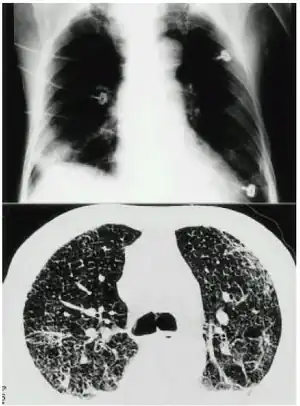

| a,b)Mercury inhalation poisoning and acute lung injury-chest images | |